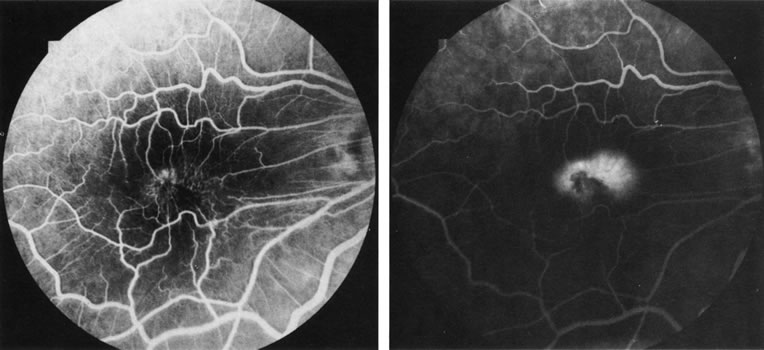

FA is generally not necessary to make the diagnosis of cystoid macular edema (CME). A history of recent cataract surgery, diabetes, uveitis, or other predisposing conditions is usually obtained. Clinically, the patient presents with retinal thickening, often with clinically evident cystic changes. FA reveals a characteristic petaloid collection of fluorescein that confirms the diagnosis, which has been shown histologically to reflect accumulation of fluid in the extravascular component of the outer plexiform layer.239 When FA demonstrates leakage from the optic nerve, this suggests an inflammatory etiology for the CME (Fig. 36). Although this sign is reliably present in CME associated with cataract surgery, penetrating keratoplasty, or posterior uveitis, it is not characteristically present in diabetics or in idiopathic CME. FA can also demonstrate dilated macular capillaries as a cause of CME in diabetes (Fig. 37). Different conditions that may cause CME include Irvine-Gass syndrome, previous penetrating keratoplasty, any inflammatory condition that involves the posterior segment, peripheral rhegmatogenous retinal detachment, peripheral cryotherapy, malignant melanoma, topical epinephrine, tapetoretinal degenerations, juxtafoveal telangiectasia, occult central retinal vein occlusion, nicotinic acid maculopathy, and idiopathic CME.

Fig. 36. Cystoid macular edema (CME). This patient had bilateral vitritis and CME. A. Early-phase photograph of the right eye reveals telangiectasia of the perifoveal retinal capillaries with some early leakage visible temporally. B. Mid-phase photograph of the left eye reveals more intense fluorescence leakage. C. Late-phase photograph of the left eye demonstrates cystic accumulation of fluorescein in a classic “petaloid” configuration. The late-phase staining of the optic nerve head in this fluorescein angiogram suggests an inflammatory cause of the CME.

Fig. 37. Cystoid macular edema in diabetes. A. Background diabetic retinopathy with multiple microaneurysms that hyperfluoresce and with dot and blot hemorrhages that block fluorescence. B. Late-fluorescein angiogram reveals accumulation of exudate in a cystoid pattern around the foveal avascular zone. (Courtesy of Dr. Kenneth G. Noble.)